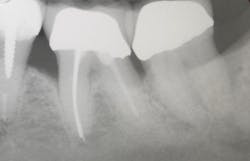

A patient had four quadrants of scaling and root planing in the office of her general dentist. Subsequently, three maxillary anterior implants were placed. The patient was scheduled every six months for periodontal maintenance visits. Radiographs taken prior to the scaling and root planing (figure 4) revealed moderate periodontitis with slight vertical bone loss involving the mandibular left first molar. A deep vertical osseous defect on the distal of the second molar was present.